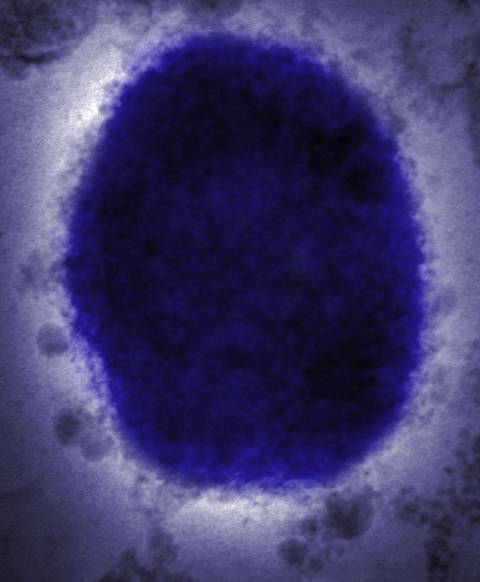

猴痘是由猴痘病毒所引起的,它与天花属于同一病毒家族,但严重程度要轻得多,专家们说其传染性很低。